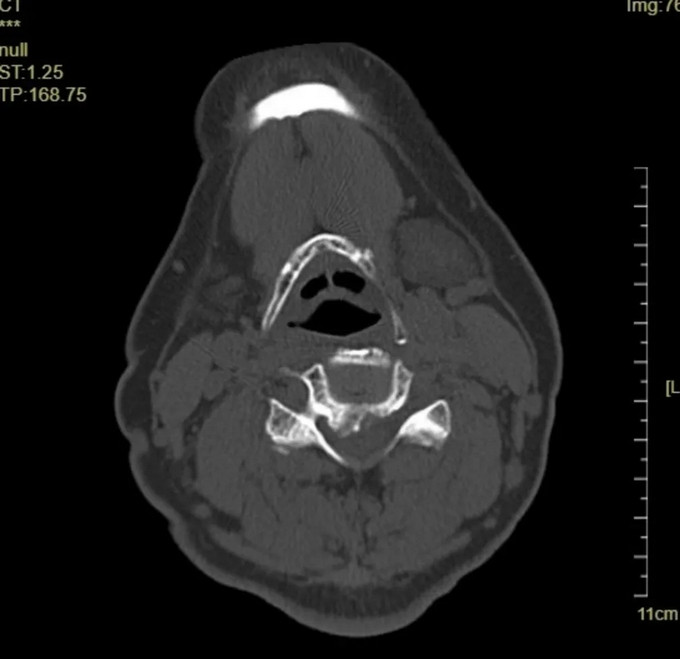

术前影像

颈椎CT矢状位

颈椎CT横断位 可以看到明显突出的骨赘

颈椎MRI横断位

入院影像学检查示:

C4-5、C5-6椎间盘突出伴钙化,C4-5、C5-6 层面脊髓变性。